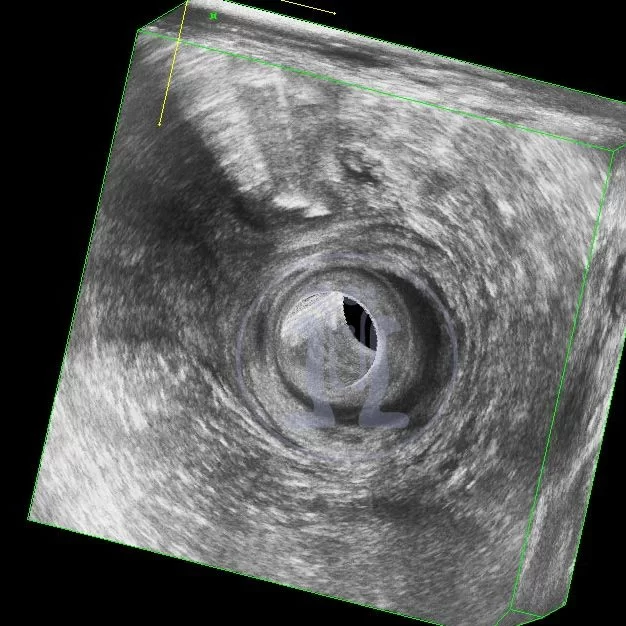

Αποτυχία πρωτοποριακής!! χειρουργικής επέμβασης για περιεδρικό συρίγγιο πάνω από 4 φορές.

O συνάδελφος είχε υποσχεθεί ποσοστό επιτυχίας 90%- καλύτερο ακόμη και από το 70% του επινοητή της μεθόδου (K. Wilhelm). Ομως η εγχείρηση απέτυχε πάνω απο 4 φορές!!!